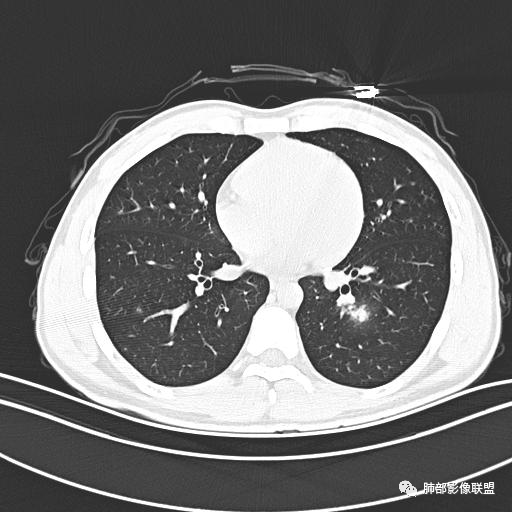

小强:青年,发热,皮疹;双肺散在结节,周围磨玻璃,点晕征,疱疹病毒感染,鉴别荚膜组织胞浆菌,结核。 大雄:青年,急性起病,发热伴全身皮疹2天,抗病毒治疗体温有下降。双肺随机分布大小不等类圆结节,“点晕征”。考虑水痘-疱疹病毒(VZV)血播询问接触史,查体皮疹分布以及形态基本可诊断。 王开金江津中心医院呼吸科:青年男性,起病急,病程短,以发热,皮疹为首发症状,感染指标以单核细胞升高为主,胸部ct双肺多发结界,周围有晕,点晕表现,随机分布,同意於老师意见,水痘疱疹病毒血流感染累及肺。 王秀仙:双肺多发大小不等结节,周围有晕,边缘模糊,呈点晕征表现。青年,急性起病,发热伴全身皮疹2天,抗病毒治疗体温有下降。考虑疱疹病毒。鉴别荚膜组织胞浆菌。 傅昌瑜:19岁男性,发热、全身皮疹2天,单核细胞增高,双肺多发结节,结节边缘见边界不清磨玻璃影。点晕征+发热、全身皮疹+单核细胞增高——考虑水痘-带状疱疹病毒肺炎。 一切∮随缘:年轻男性,发热,皮疹两天,实验室,CRP,PCT增高,影像:双肺多发散在磨玻璃结节,边界欠清,大小不等,呈点晕征改变,以血管束周围分布为主,局部血管束略增粗,其它无明显改变,考虑:1:病毒性肺炎(水痘疱疹病毒?不知道皮肤有无改变)2:真菌(组织胞浆菌,血管侵袭性肺曲霉)3:GPA4:寄生虫(实验室没有看到嗜酸细胞增高) 赵山河:双肺散在结节,周围有晕,边缘模糊,呈点晕征表现。青年,急性起病,发热伴全身皮疹2天,抗病毒治疗体温有下降。考虑水痘—疱疹病毒感染。洪桥爱:青年男性,发热、皮疹2天,伴瘙痒,皮疹于面部首发,之后进展至全身,虽然没有对皮疹进行描述,但是从出疹时间及皮疹进展情况,伴瘙痒,应该就是个水痘患者;CT提示双肺随机分布结节影,部分结节伴有边界不清晕征,考虑水痘血播肺。 刘强:年轻男性,急性起病,皮疹,发热,抗感染治疗体温下降,说明有效。影像表现为散在点晕征,感染类疾病谱(疱疹病毒,真菌,结核),结合年龄,皮肤皮疹,考虑水痘-疱疹病毒性肺炎。 小兜:男性,19岁,发热皮疹两天,颜面部至全身,CRP,降钙素及单核增高。CT示双肺散在小结节,周围伴磨玻璃影,点晕征,考虑为水痘-带状疱疹病毒(varicella-zoster virus,VZV)肺炎 必有路:青年,皮疹+发热+“点晕征”→水痘-疱疹病毒(VZV) 许慧良:青年男性患者,发热、皮疹2天,体温最高38.5℃,第3天皮疹扩展至全身,伴瘙痒,胸部CT:双肺多发随机分布的小结节,结节周边见边界模糊的晕征,考虑水痘病毒感染流心明智:男,19,急性起病,发热伴全身皮疹2天。出疹顺序头→全身,抗病毒有效。胸部CT:两肺多发大小不等类圆形实性小结节影,随机分布,结节周围环绕GGO,边界模糊,呈点晕征。出疹特点是关键,未提示。考虑:血播病毒性肺炎,水痘-疱疹病毒?麻疹?鉴别荚膜组织胞浆菌、TB、血管炎、寄生虫等。 浪迹天涯:病灶多为5-10mm大小结节,结节周围可见磨玻璃样的晕环,常多发,可分布于肺内任何区域,考虑水痘—带状疱疹病肺炎如果短时间内有新的一个区域浸润,更加能说明,